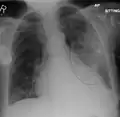

Right upper lobe pneumonia as marked by the circle. -

Left upper lobe pneumonia with a small pleural effusion.